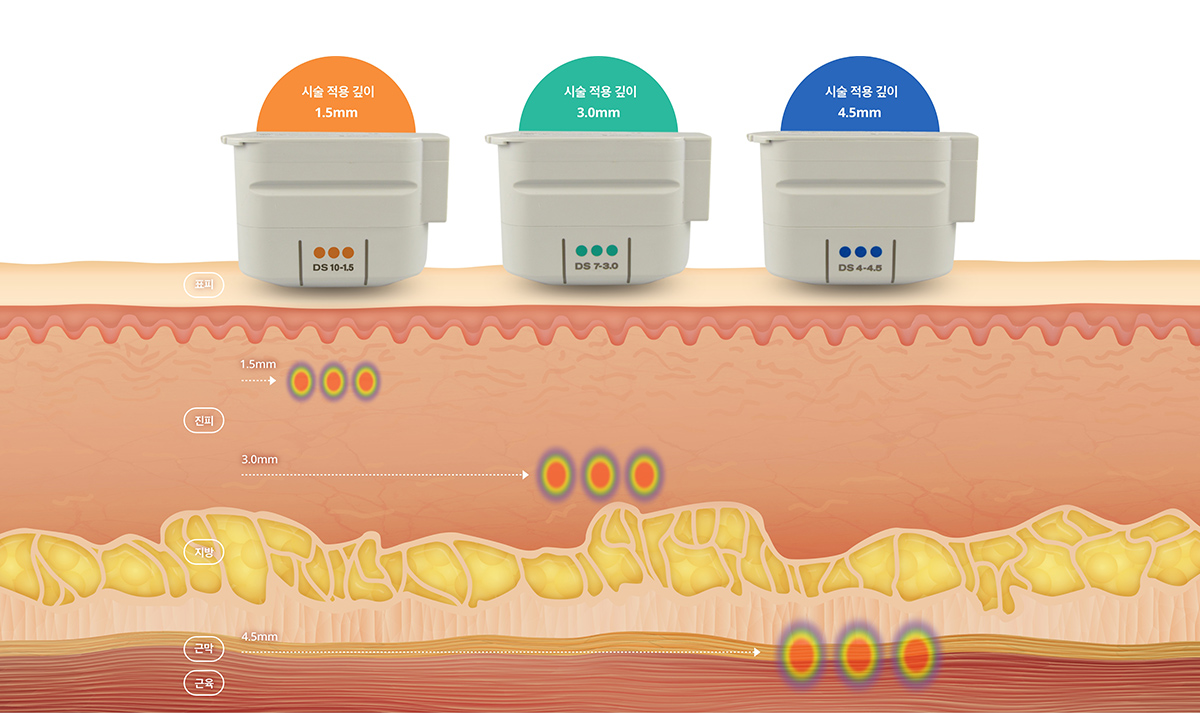

울쎄라피 프라임은 1.5mm, 3.0mm, 4.5mm

세 가지 팁으로 진피부터 근막층(SMAS)까지

타겟팅이 가능해 피부 상태에 따라 맞춤 시술이 가능합니다.